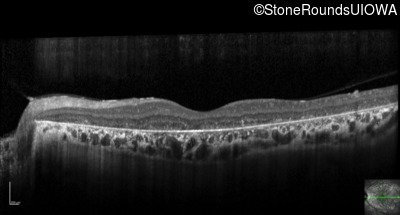

Optical Coherence Tomography - Left - 10/300 sc

Exemplar / OCT Stack

OCT Stack